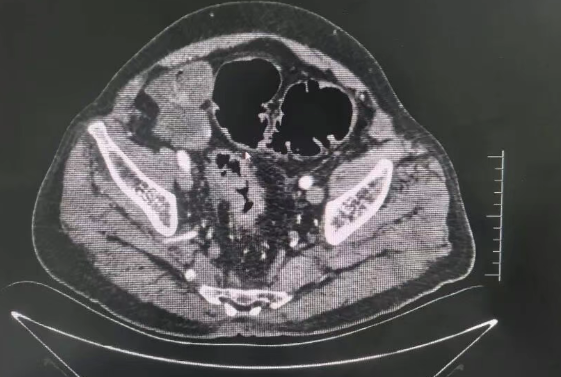

*患者CT轴位影像图

1.轴位图像(上图):右下腹阑尾区可见一个囊性包块,大小约53×40mm,内部密度低,充满粘液。影像中心医生凭借丰富经验,第一时间将病灶定位至阑尾起源。

2.增强扫描(上图):增强后仅囊壁轻微强化,内部粘液无强化。我院采用的多期增强扫描技术,精准呈现了这一典型特征,为鉴别诊断提供了关键依据。